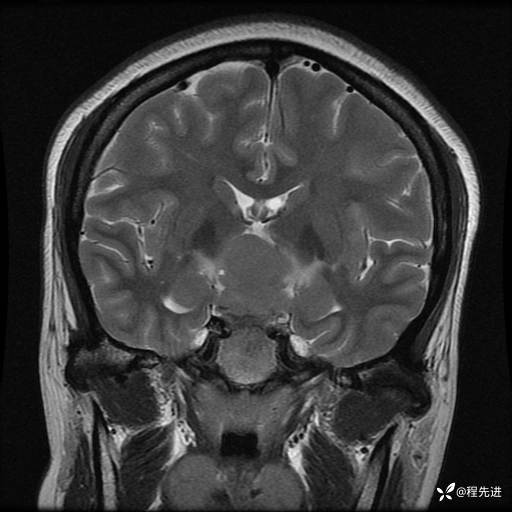

MRI平扫+增强:

T2: